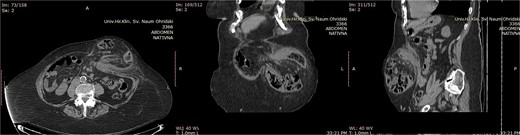

This retrospective observational case series included patients treated for midline incisional hernias between January 2017 and December 2023 with the Chevrel technique. All the patients were diagnosed with physical examination (Fig. 1) and abdominal computerized tomography (CT) scans (Fig. 2). The midline incisional hernia was classified according to the EHS classification [11].

Abdominal computerized tomography scan of a patient with M3W2 incarcerated incisional hernia. The incarcerated loop of the transverse colon is visible in the hernia sac (A-axial scan, B-coronal scan, C-sagittal scan).